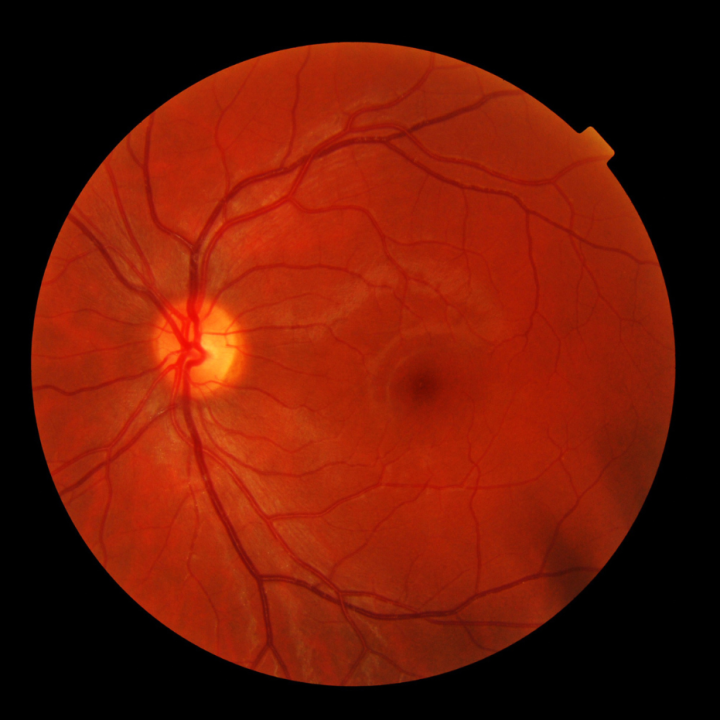

If you are living with or at risk for diabetes, a yearly dilated and comprehensive eye exam or retinal photography can help you find out about diabetes-related eye disease. Learning about diabetes-related eye disease early will help you take steps to prevent vision loss. The longer you have diabetes, the more likely you are to develop eye complications.

An eye exam lets your eye doctor (optometrist or ophthalmologist) see your entire retina. Early detection, timely treatment, and appropriate follow-up care with your eye doctor can reduce your risk for severe vision loss from diabetes-related eye disease.